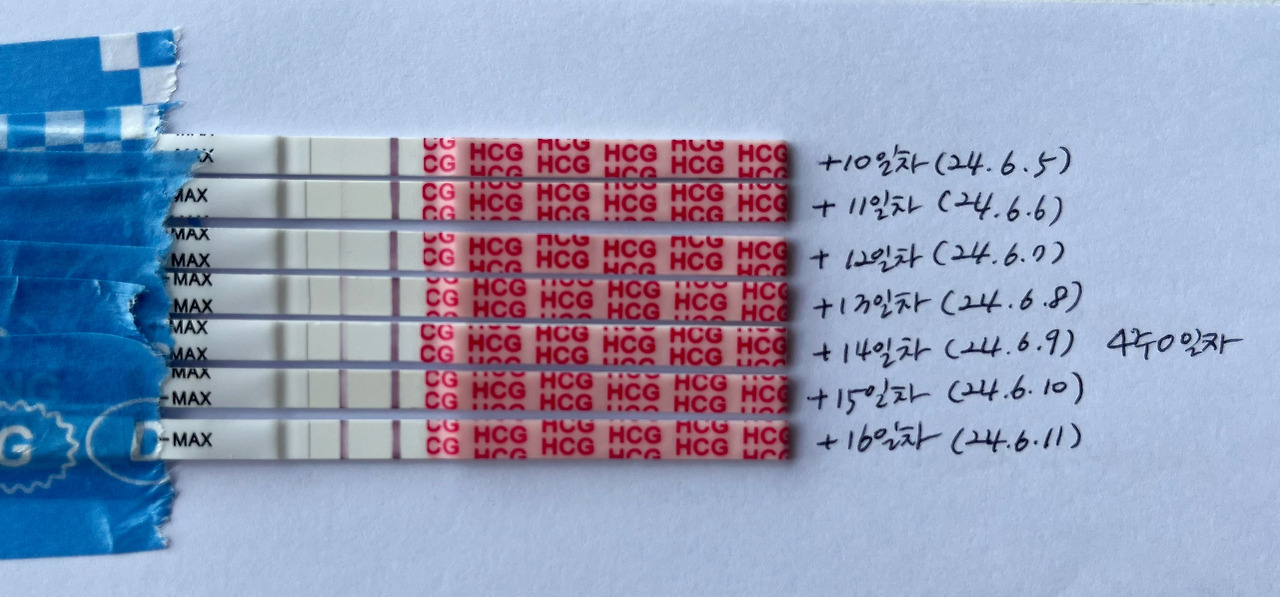

배란 10일차 ~ 16일차 원포테스트

배란 10일차에 내 눈에 아주 옅게 보이던 줄이, 배란 11일차에 얇은 선으로 보이면서 임신을 직감했다.

물론 너무 확신을 하기는 일러서 계속 매일 테스트 하면서 임신이 잘 유지되고 있는지를 지켜보았다.

배란 14일차 생리예정일엔, 라인이 아직 많이 진하진 않았지만 생리가 멈춰서 기분이 좋고 너무 신기했다. ㅎㅎ

배란 15일차 되니 이전 보다는 많이 진해진 것 같아 안심이 되었다.